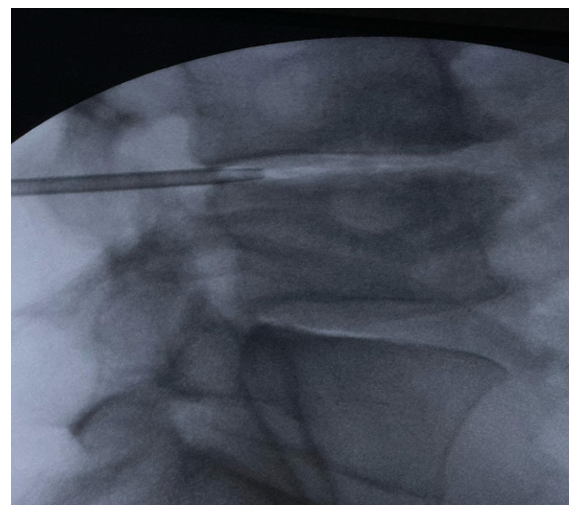

The traditional surgical approach—open discectomy—aims to decompress the nerve root and alleviate pain. However, in recent years, numerous minimally invasive techniques have emerged, including percutaneous mechanical and laser discectomy, as shown in figure 1. These procedures aim to reduce tissue damage and recovery time, while maintaining efficacy. Despite encouraging results and good patient acceptance, these techniques have encountered skepticism in parts of the surgical community. Among them, endoscopic foraminal discectomy has gained widespread recognition. In this article, we present a case of lumbar herniation treated with a percutaneous mechanical discectomy system, describing the technique in detail and reporting clinical follow-up.

Figure 1: Spinal Needle Positioning under Fluoroscopic Guidance during the Percutaneous Discectomy Procedure